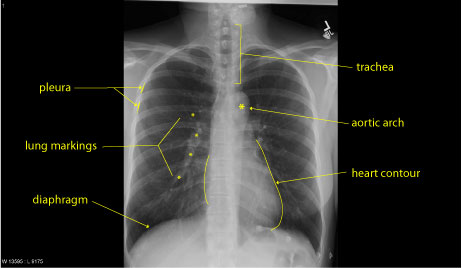

A part of the upper torso, the chest is the are. Normal Chest X-Ray and Lung - radRounds Radiology Network

Normal Chest X-Ray and Lung - radRounds Radiology Network from storage.ning.com